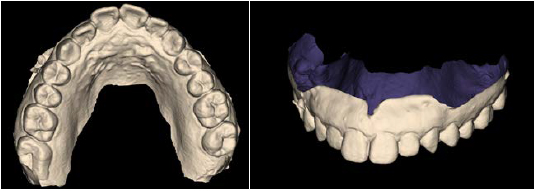

Режим сканирования модели.

Возможность сохранения исследования в STL формате для дальнейшего сочетания с CAD/CAM технологиями или создания и печати хирургического шаблона.

Экспортированные STL данные подходят лоя проектирования временных протезов, имплантатов и для ортодонтического лечения.

Экспорт STL-файлов

Возможность сохранения исследований в STL формате для дальнейшего сочетания с CAD/CAM технологиями или создания и печати хирургического шаблона.